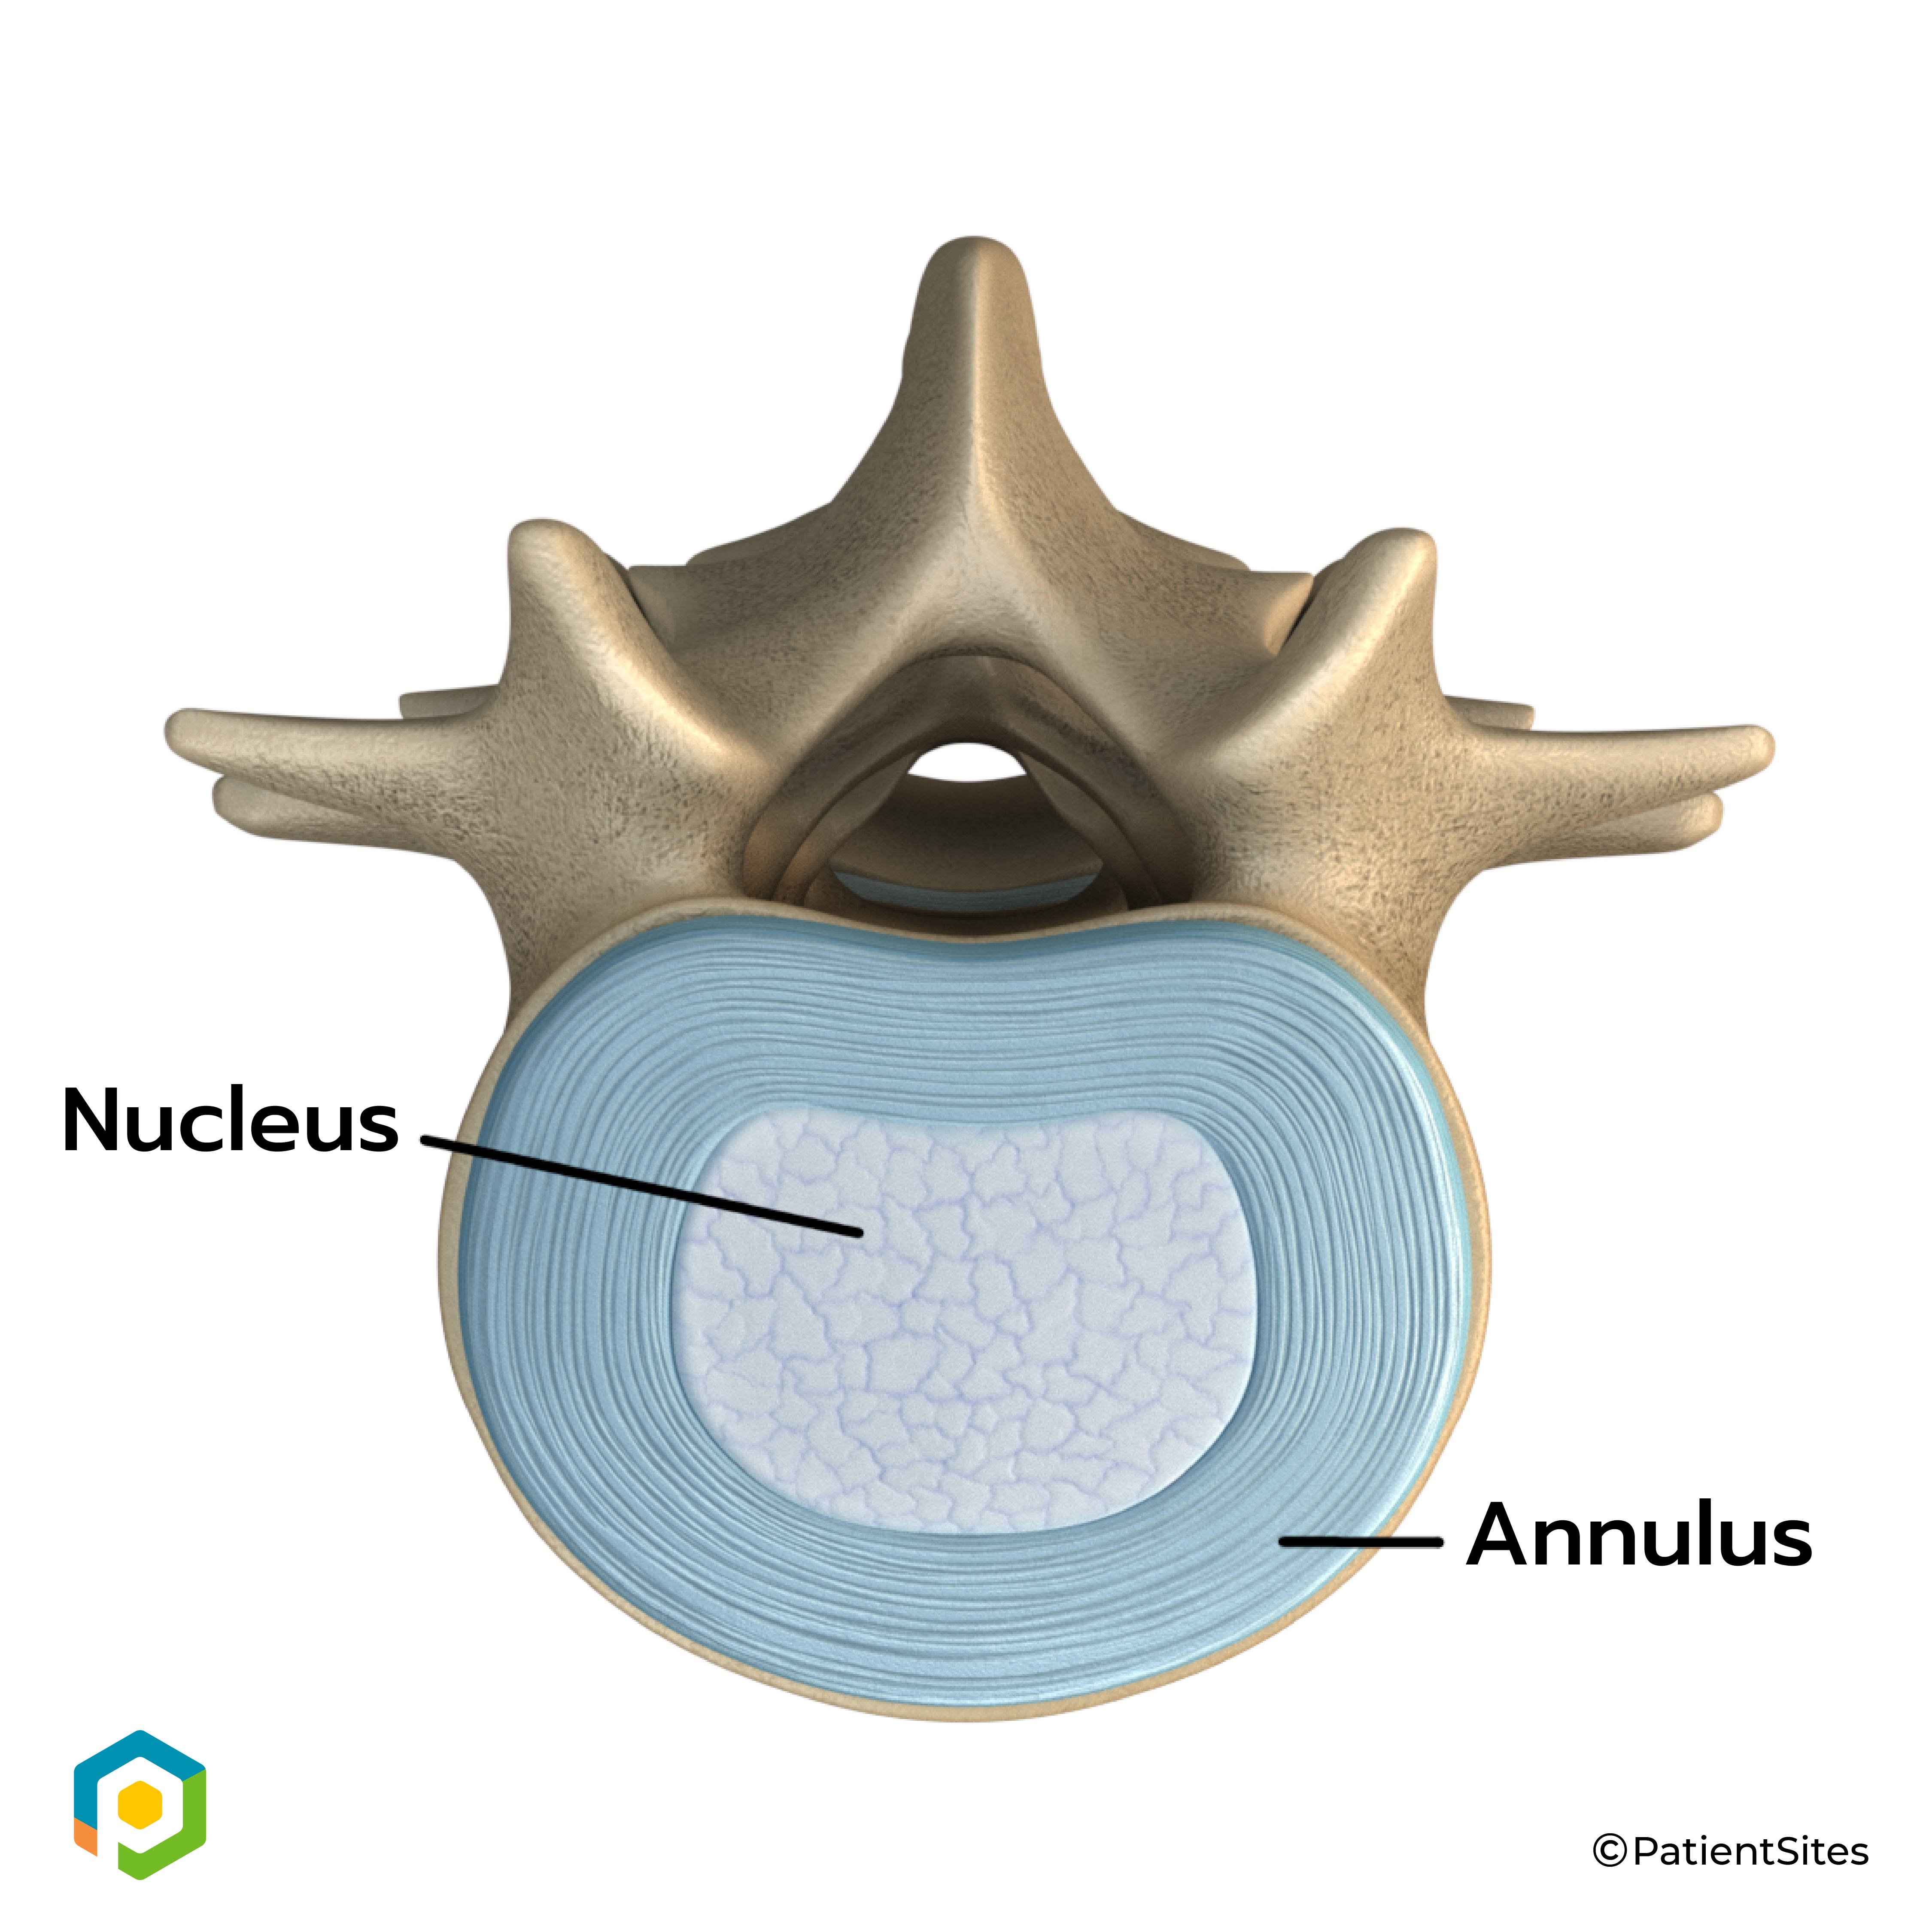

An intervertebral disc is made of two parts. The center, called the nucleus, is spongy. It provides most of the disc's ability to absorb shock. The nucleus is held in place by the annulus, a series of strong ligament rings surrounding it. Ligaments are connective tissues that attach bones to other bones.

Two Parts of Intervertebral Disc